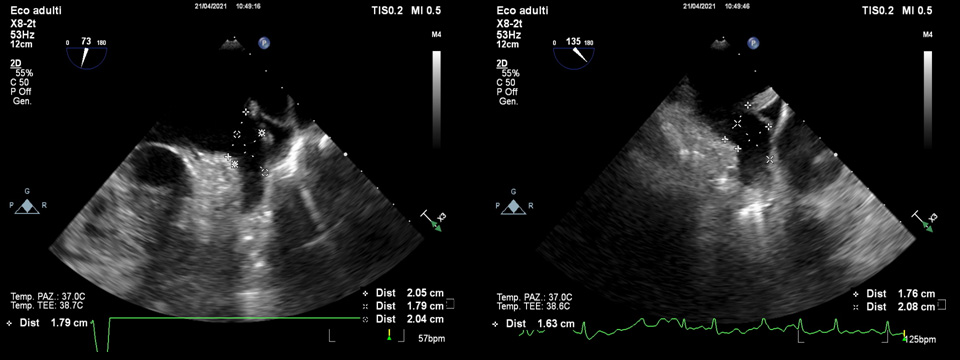

A full 0–135

Fig. 4.By use of multiplanar TOE, full 0–135